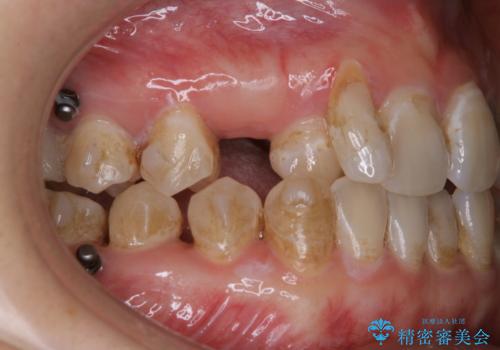

インビザライン矯正中にPMTCでコーヒーによるステインの除去

- コーヒーを毎日頻繁に飲むため、ステインがついてしまうとのことでした。全体的に頑固なステインの付着が見られたため、PMTC60分コースを行いました。

PMTC(保険外治療)は、毎日の歯磨きで落としきれない汚れや、コーヒ、紅茶・タバコのヤニなどの着色も除去します。目には見えない歯と歯の間・歯肉の境目・インビザライン中はアタッチメント周囲などに残っているプラーク(歯垢)もしっかり取り除きます。PMTCでは専門的な機械や材料を使用して、徹底的に汚れを除去するため、虫歯・歯周病・口臭予防などにつながります。